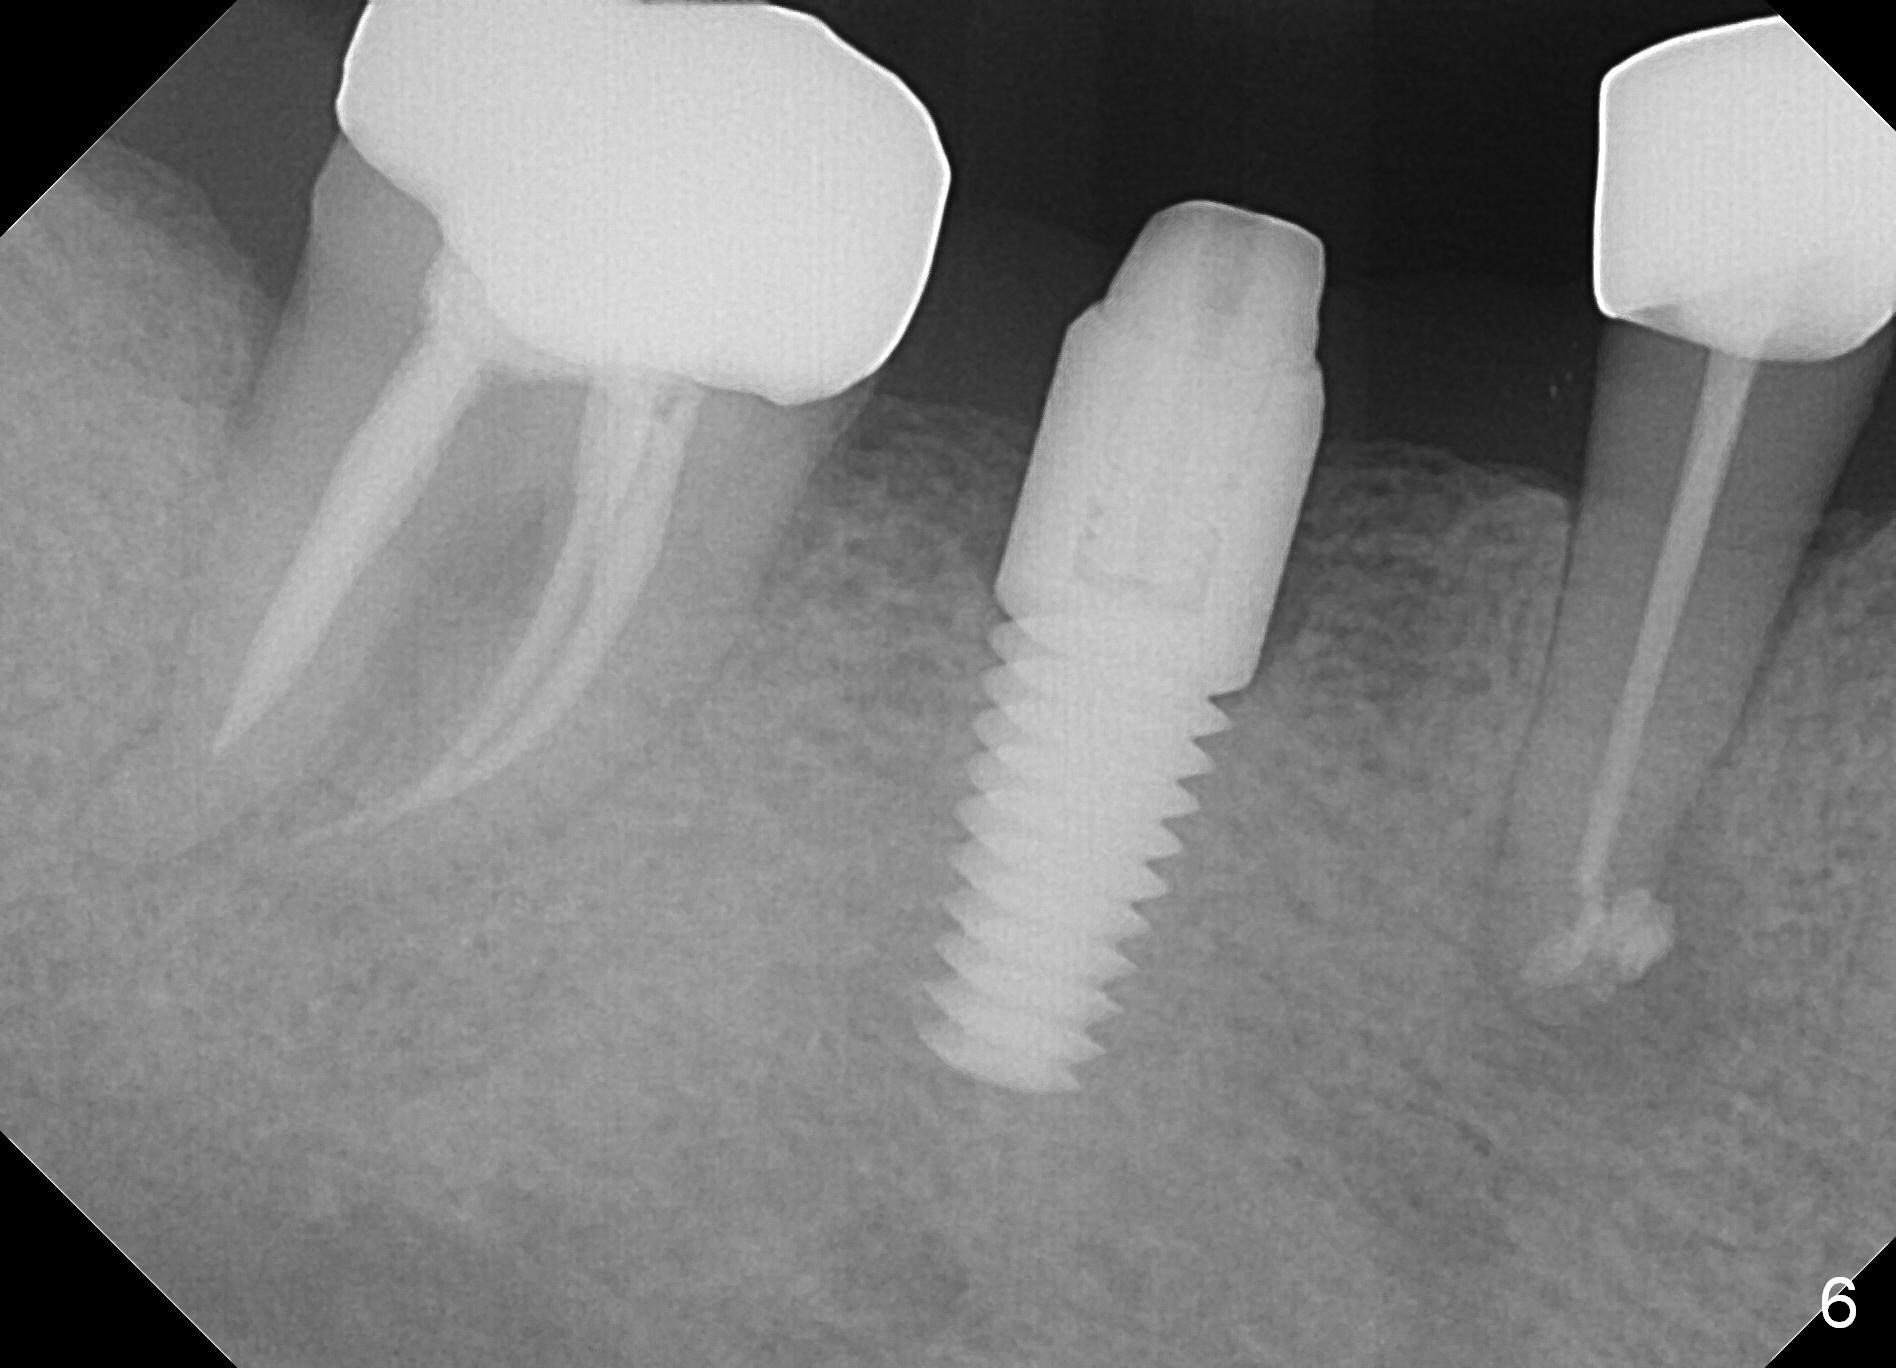

A 47-year-old man has history of bruxism, chipping porcelain from #29-31 FPD (Fig.1). Following sectioning the FPD, osteotomy is created (Fig.2: 5x14 mm drill) for placement of a 5x14 mm tissue-level implant (Fig.3,4). A 4x3 mm abutment (Fig.5 (lingual view) A) with 3 vertical slots (* for increased retention) is placed to retain periodontal dressing. The crown over the implant has dislodged 3 times over 28 months post cementation (Fig.6). It appears that the top of the abutment is too rounded. Clinical exam shows that the abutment height can be more, although the tooth #3 is supraerupted (Fig.7 (orthodontic intrusion is not indicated because of furca infection)).

Pre-impression photos show supraerupted #3 (Fig.7). Clearance is a little more than 1 mm between the mesiopalatal cusp of #3 (Fig.7 *) and the rounded abutment (Fig.8). Removal of the abutment turns out to be easy. Reduction is confined to the opposing tooth (slopes of the cusps). No occlusal reduction is done for the new abutment as mentioned above except for 2 retention grooves. One-mm reduction ring barely passes the occlusal clearance (Fig.9). No cement is applied to the abutment in case a longer abutment may be required. Bone density seems to remain the same or increase after cementation of a new crown (Fig.7). The redo crown remains in place 1 year post cementation.